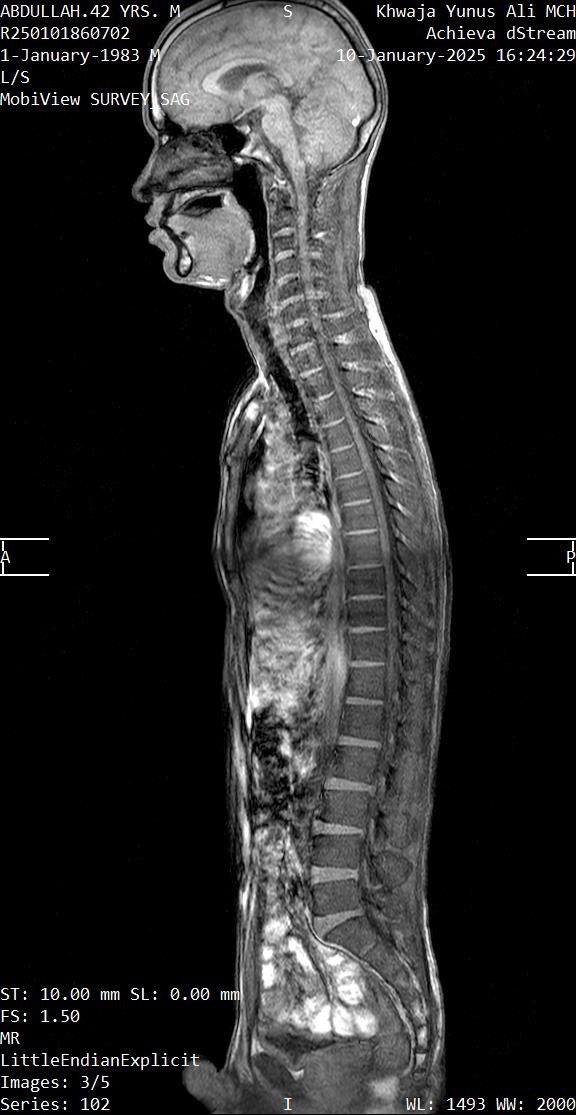

- ইমেজিং: X-Ray (হাড়ের পরিবর্তন), আলট্রাসনোগ্রাফি (USG) বা MRI (নরম টিস্যু/কার্টিলেজের বিশদ)।

হঠাৎ তিনি জানান, ৬–৭ বছর আগে ধানের বস্তা মাথায় নেওয়ার সময় ঘাড়ে আঘাত পান 😥 এবং কয়েক দিন বিছানায় থাকতে হয়। ব্যথার ওষুধ খেয়ে সহনীয় হয়, কিন্তু তারপর থেকেই ঘাড়ে ও হাতে ব্যথা শুরু হয়। কিছুদিন পর থেকেই Shortness of Breath ও Sleep Apnea শুরু হয়। 😥😥😥😥

আমি চিন্তা করলাম — এটি Phrenic Nerve সমস্যার কারণে হতে পারে।

Phrenic Nerve কী?

Phrenic nerve হলো আমাদের Diaphragm (শ্বাস নেওয়ার প্রধান পেশী)-এর মোটর ও সেন্সরি নার্ভ। এটি স্পাইনকর্ডের C3 থেকে C5 ভার্টিব্রা থেকে উৎপন্ন হয়ে ঘাড় ও বুকের খাচা হয়ে ডায়াফ্রামে পৌঁছে।

এই নার্ভের ক্ষতি হলে ডায়াফ্রামের কার্যক্ষমতা হ্রাস পায়, এমনকি সম্পূর্ণ বন্ধও হয়ে যেতে পারে।

যেহেতু রোগীর ইতিহাসে ঘাড়ে আঘাত ছিল এবং সমস্যা ঐ অঞ্চলেই, সেহেতু Phrenic Nerve Injury হওয়ার সম্ভাবনাই বেশি। তার লক্ষণও এর সাথে মিলে যায়।